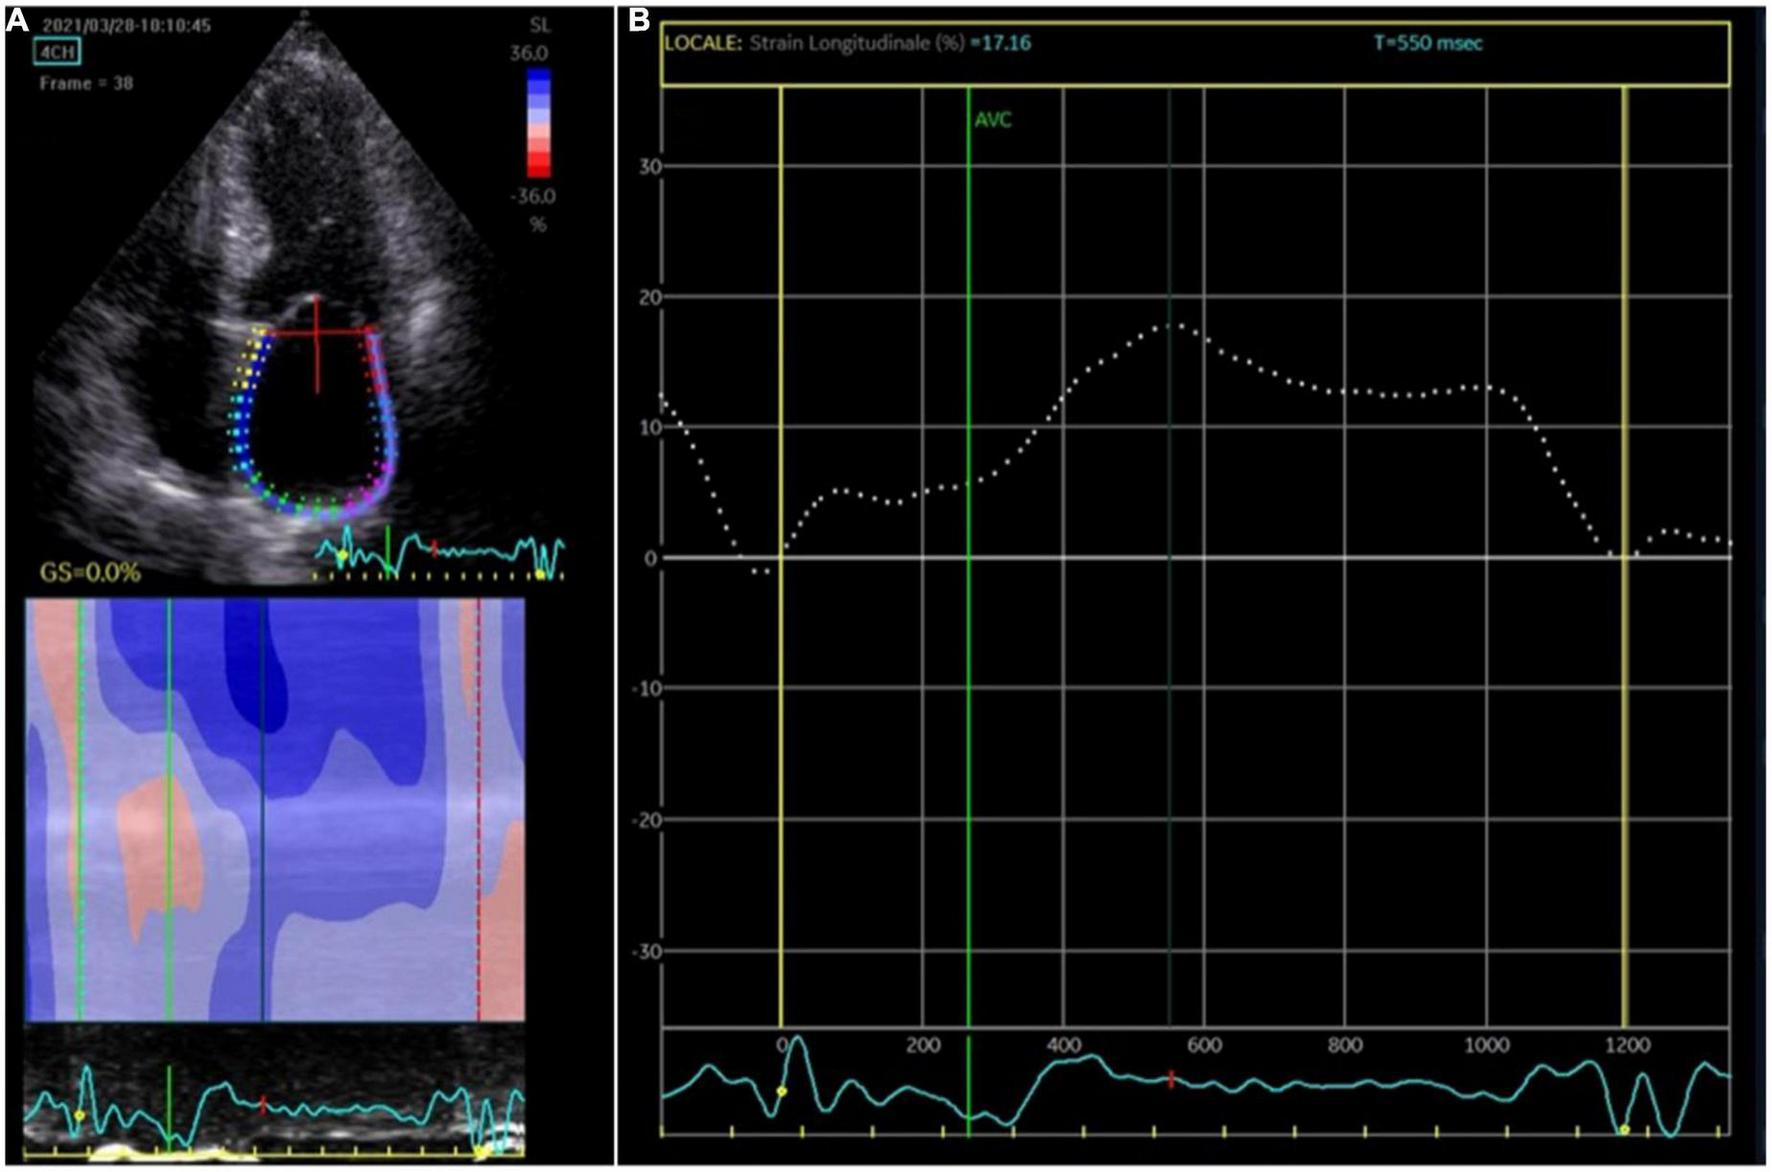

Two-dimensional speckle tracking echocardiography was performed with a standard protocol following current guidelines (10). The apical four-chamber view was utilized for the strain measurements of LA and LV. Briefly, first the LA endocardium edge was traced manually and then the tracings based on the 2D STE were generated by the software, Figure 1. The mean deformation (strain) expressed in percentage was then calculated by the software. The reservoir function of the LA (LA reservoir strain) was calculated as the maximal wall deformation of LA during LV systole as compared to the end diastole, that was considered as preset reference point (11). 2D STE LA strain refers to reservoir strain if not otherwise specified. In patients with permanent AF, atrial strain was performed during ongoing AF. In patients with non-permanent AF, atrial strain was performed during sinus rhythm. Global longitudinal strain (GLS) of LV was measured as the longitudinal shortening of the myocardium (change in length compared to the baseline length).

Figure 1. Atrial strain measurement. (A) The apical four-chamber view was utilized for the strain measurements of the left atrium (LA); the edge of the LA endocardium was manually traced. (B) The software generated tracings based on the 2D strain of LA. The mean deformation (strain) is expressed in percentage and calculated by the software.